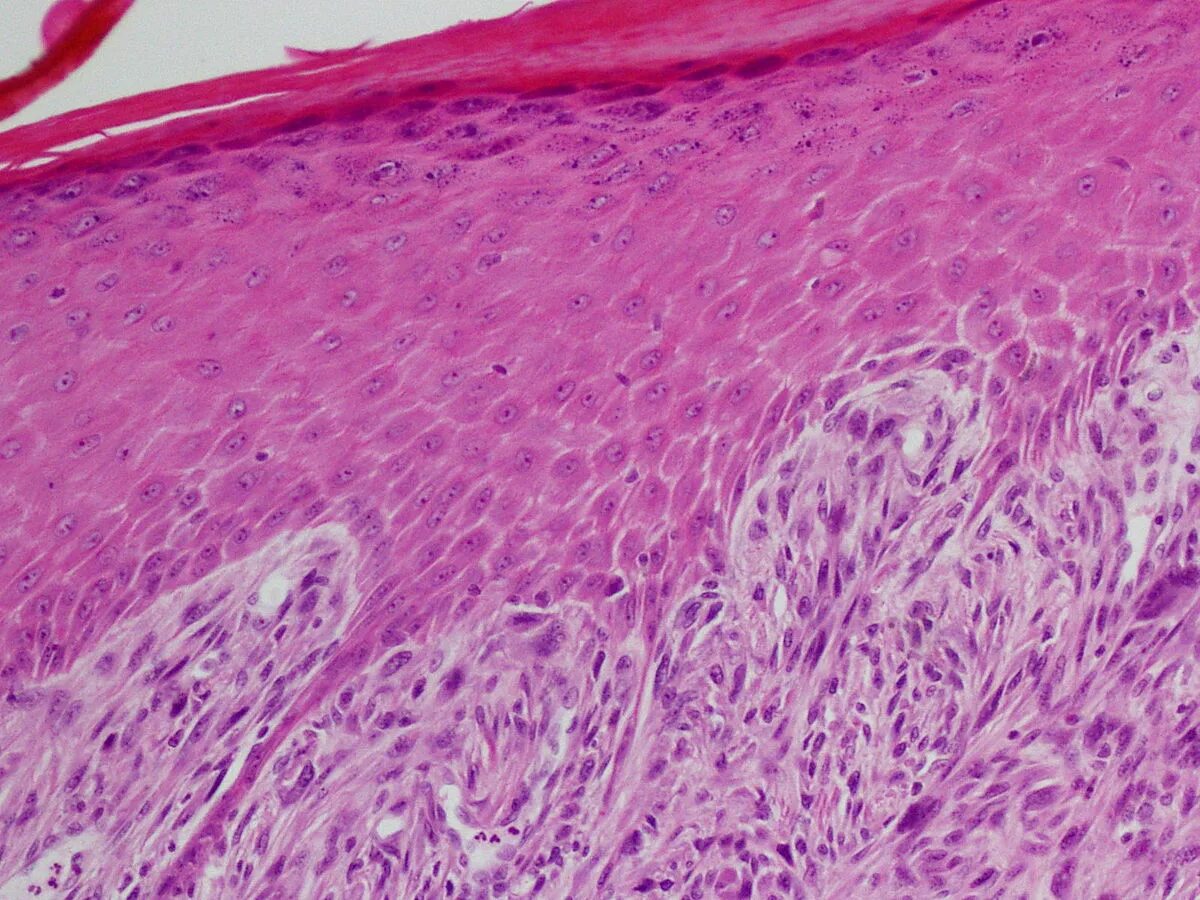

Гистология фото